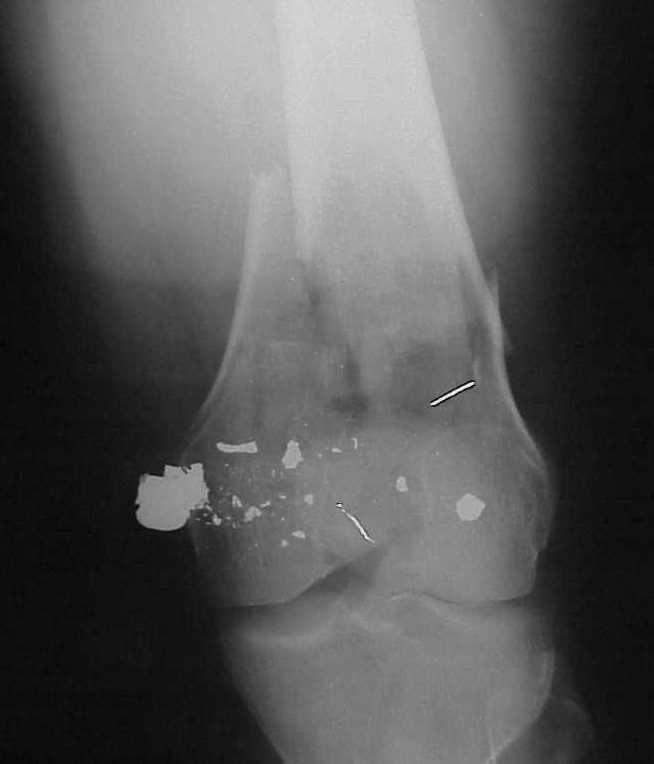

place one anterior to where IMN will go if anterior cortex if insufficient and AP screws on either side of the IMN out of the trochlea to provide some additional varus/valgus stability. I worry about the leg going into valgus w/the lack of lateral cortex.

See attached case that was done several years ago before LISS. He had comminuted trochlea and anterior blocking screws were used to prevent anterior IMN cut-out.